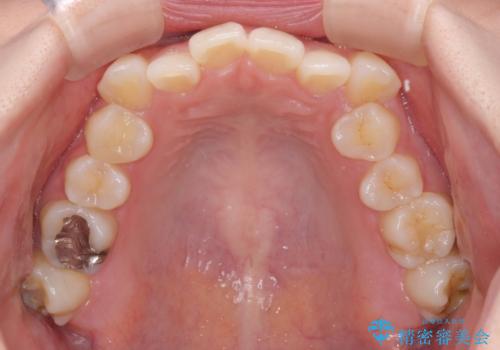

口腔内の状況を確認したところ、左右ともに下顎第二大臼歯が欠損しており、咬み合うべき上顎の第二大臼歯が著しく挺出していました。

挺出した大臼歯を元の位置に戻すことは現実的に難しいため抜歯することとし、補助装置とワイヤー装置により上顎歯列全体を後方に移動することとしました。